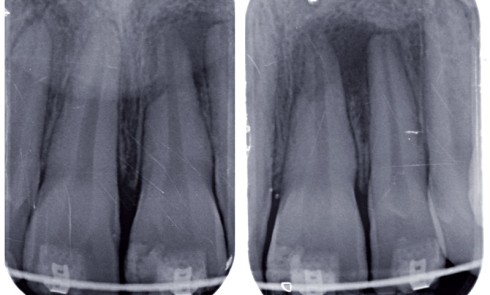

Article réservé à nos abonnés La cicatrisation de la lésion apicale d’origine endodontique

La lésion apicale ou lésion inflammatoire péri-radiculaire d’origine endodontique (LIPOE) est une des affections les plus courantes de la planète.L’étude...